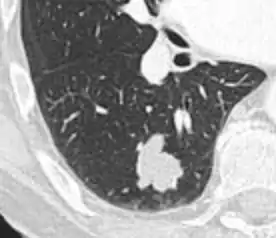

Lung nodule abutting a pulmonary cyst.[9]

• A lung nodule abutting a pulmonary cyst is a rare finding, yet indicating cancer.[9]